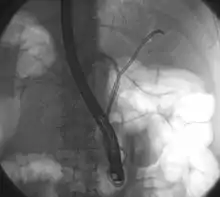

Klatskin tumor during ERCP. Wires were inserted into the left and right biliary systems. Both parts were injected through a tube with contrast, but there is no contrast visible in the area of confluence of the two systems

A Klatskin tumor (or hilar cholangiocarcinoma) is a cholangiocarcinoma (cancer of the biliary tree) occurring at the confluence of the right and left hepatic bile ducts. The disease was named after Gerald Klatskin, who in 1965 described 15 cases and found some characteristics for this type of cholangiocarcinoma[1][2][3]